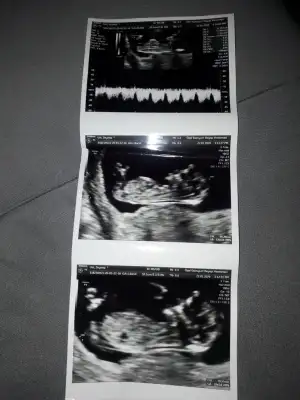

20200120_110507.jpg

Henüz cinsiyetini bilmiyorum 16 haftaya doğru belli olur dedi siz tahmininizi yine de yaparsanız sevinirim ben de öğrenince ankete katılırım

Eklentiler

• 20200120_110519.webp

20200120_110519.webp

33,7 KB · Görüntüleme: 65